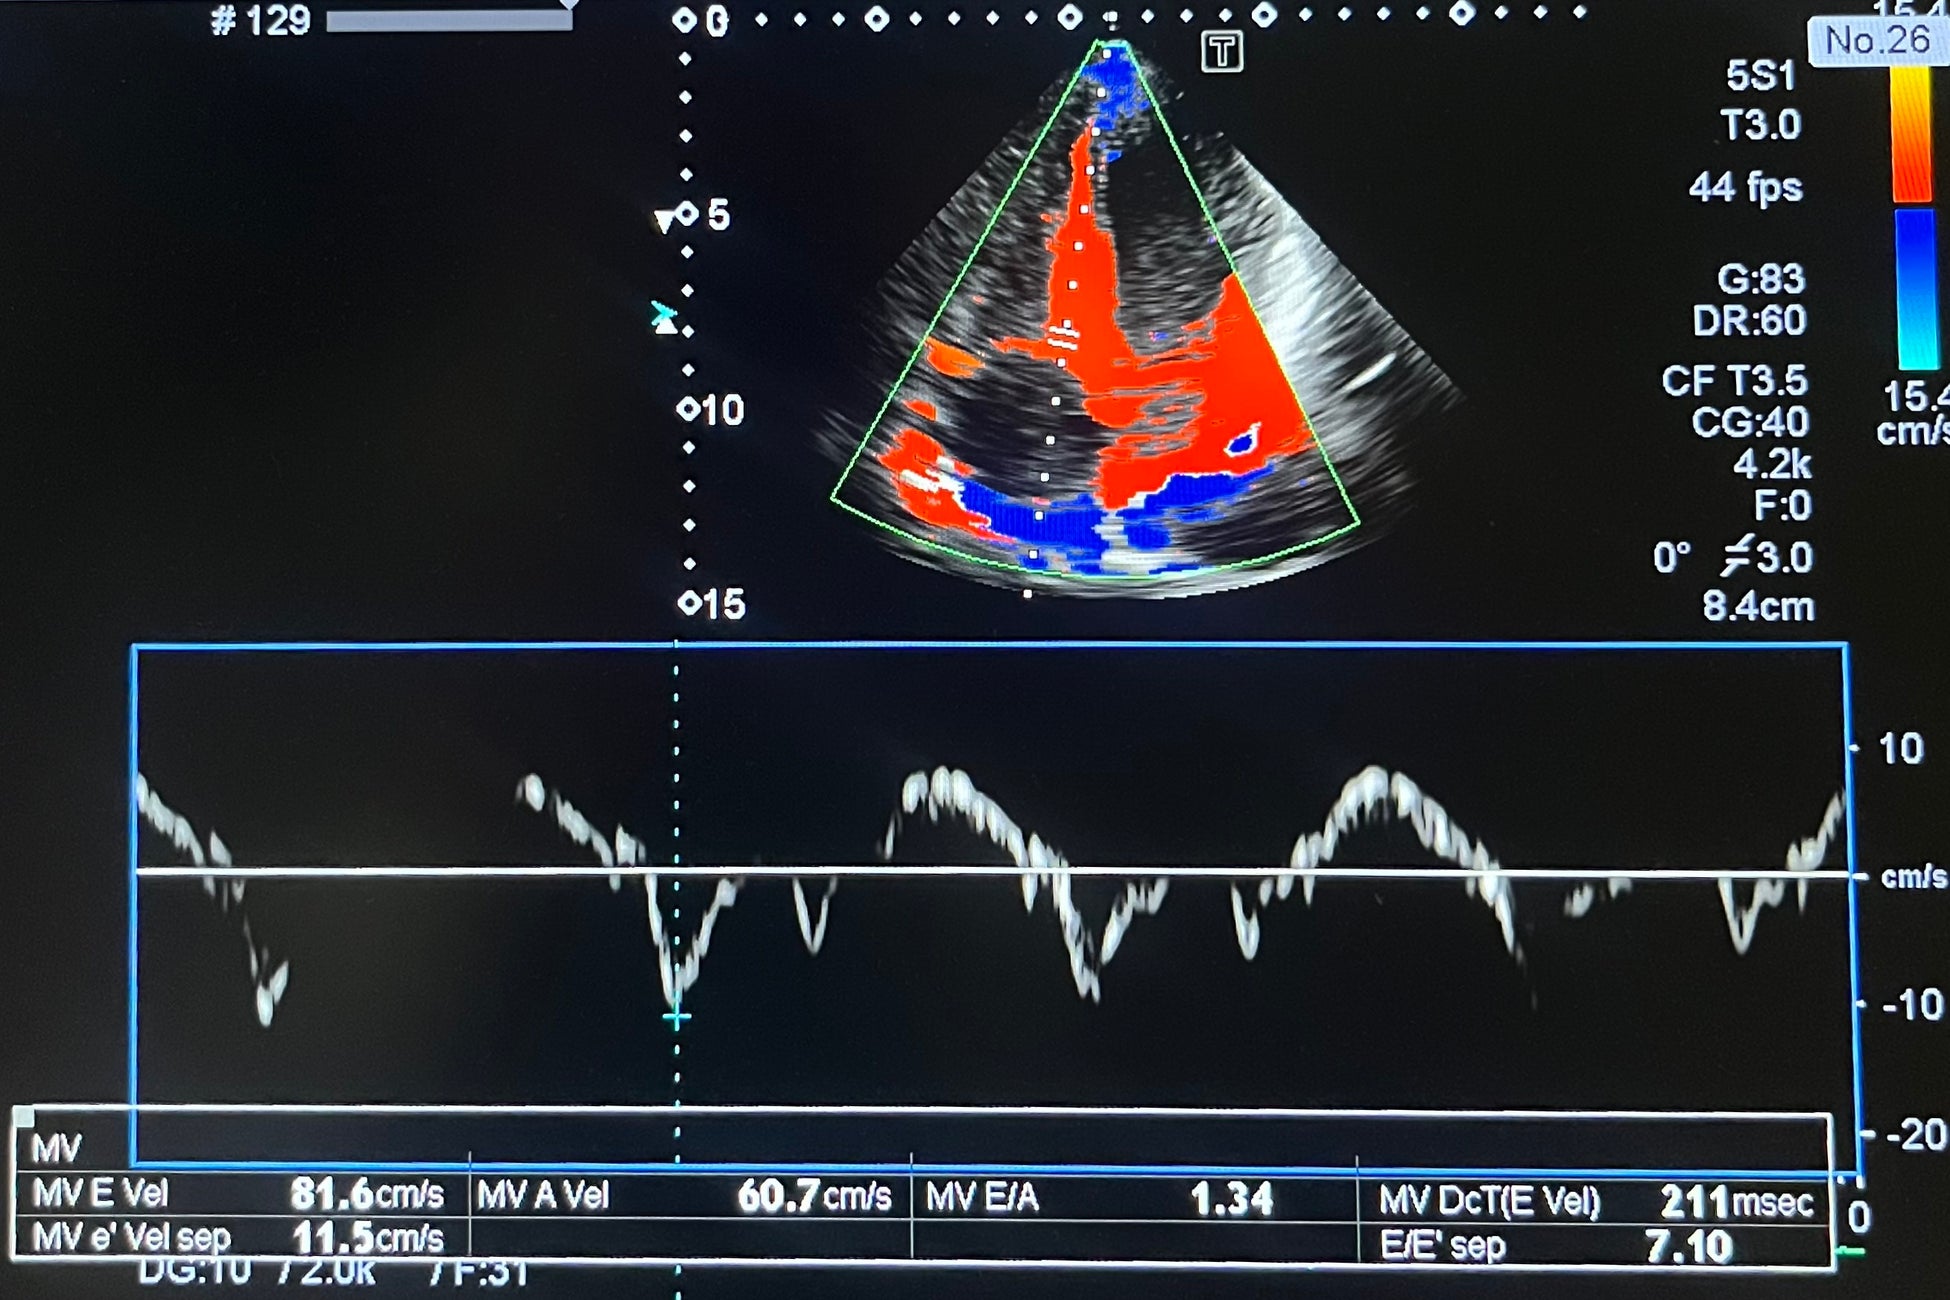

・心臓超音波

心臓の心房、心室の大きさや壁の厚さ、動きなど観察し、心肥大や心筋梗塞の範囲などを診断、心臓

の中の血液の流れ、弁の逆流がないか、弁の開閉が問題ないかも調べる事ができます。